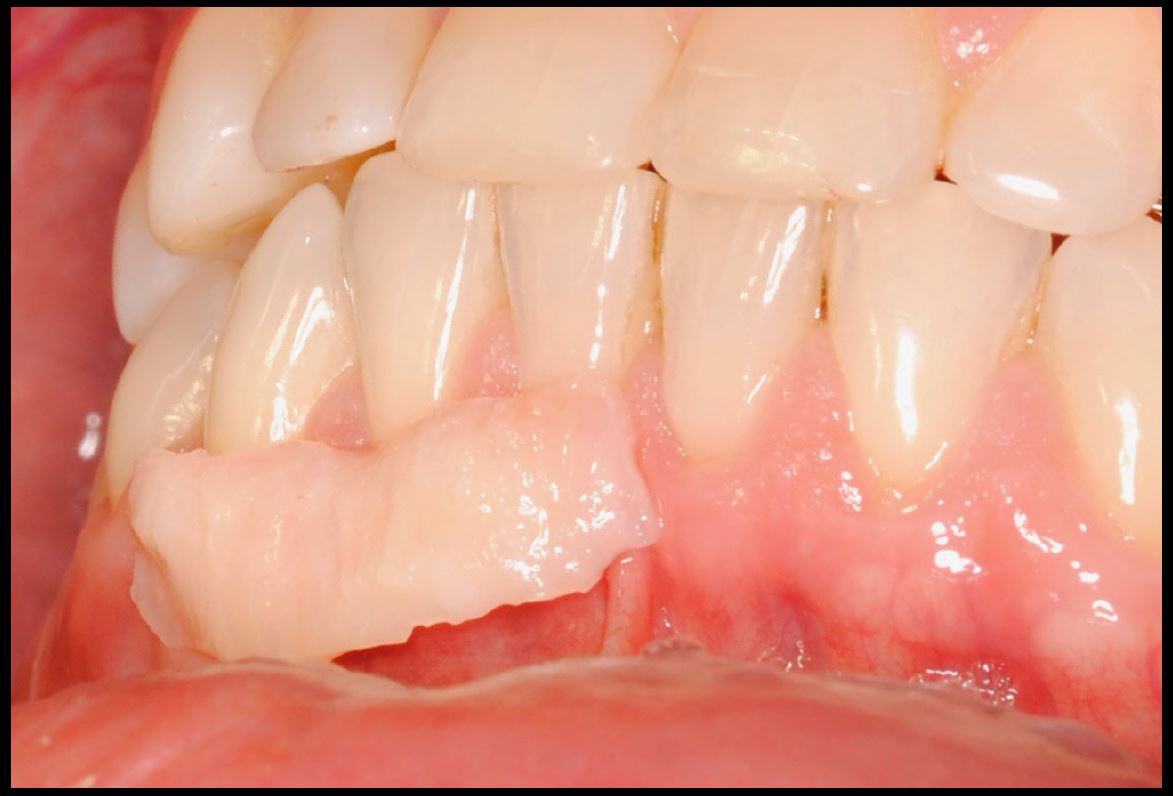

Objetivos periodontales: Mediante ingerto de tejido conectivo subepitelial de paladar con técnica de tunelización.

- Injerto de tejido conectivo libre desepitelizado de paladar + Tunelización

Fotografías del proceso: